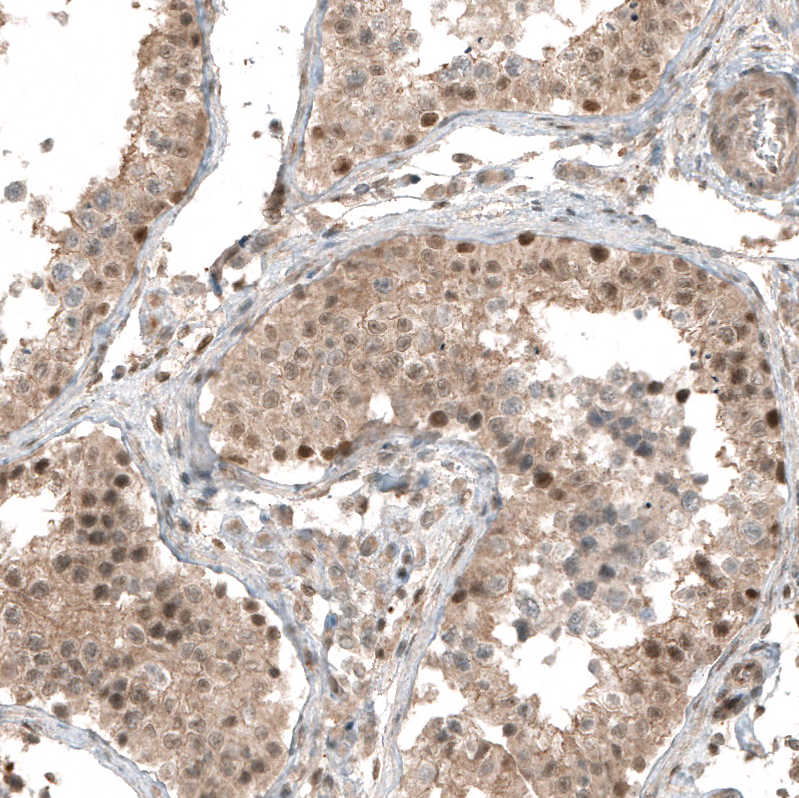

Immunohistochemical staining of human prostate shows moderate nuclear and cytoplasmic positivity in glandular cells.